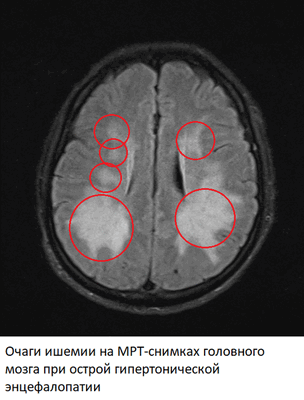

Острая гипертоническая энцефалопатия

Острая гипертоническая энцефалопатия - патологическое состояние, возникающие из-за повышенного артериального давления (АД выше 200/130 мм. ртутного столба, реже при более низком давлении). Характеризуется возникновением участков ишемии в тканях головного мозга, вплоть до образования микроскопических кровоизлияний. В норме при повышении артериального давления происходит спазм мелких артерий головного мозга, однако при острой гипертонической энцефалопатии этот же спазм может стать запредельным, что и приводит к возникновению участков тканей мозга, испытывающих недостаток кислорода. Резкое расширение спазмированных артерий ведет к отеку мозга. Острая гипертоническая энцефалопатия - предвестник геморрагического инсульта.

На МРТ-снимках признаки гипертонической энцефалопатия проявляются в виде множественных очагов ишемии/микроскопических кровоизлияний в тканях головного мозга. В ангио-режиме одновременно обнаруживается спазм одних и расширение других артерий.